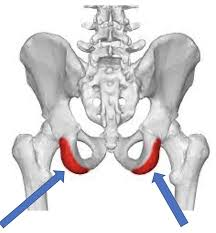

Inferior Pubic Ramus

Ischial Ramus